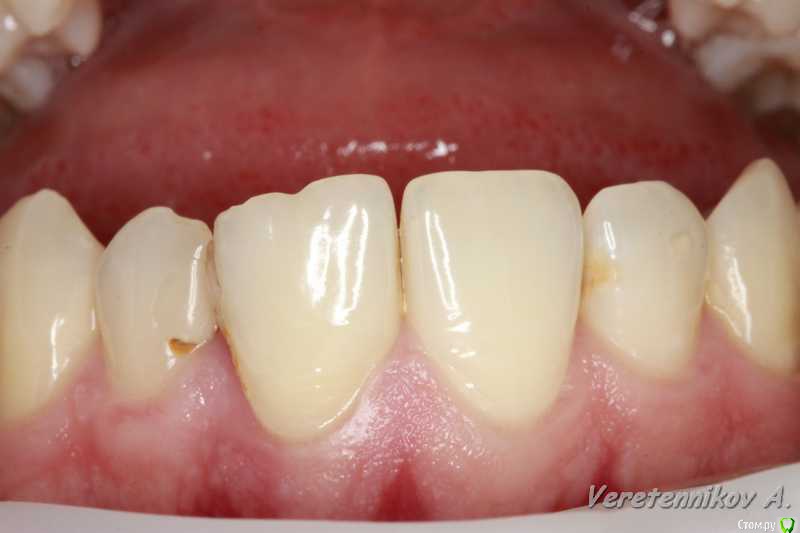

an_ver Опубликовано 15 декабря, 2015 Поделиться Опубликовано 15 декабря, 2015 Травма 21, немного сместился,удаление,имплантация SPI 4.2*13,ГенОсс+ ауто со сверла,для временной коронки использован свой зуб)),немного укоротили реж.край,чтоб не травмировать,унифлекс 5/0 18 Ссылка на комментарий